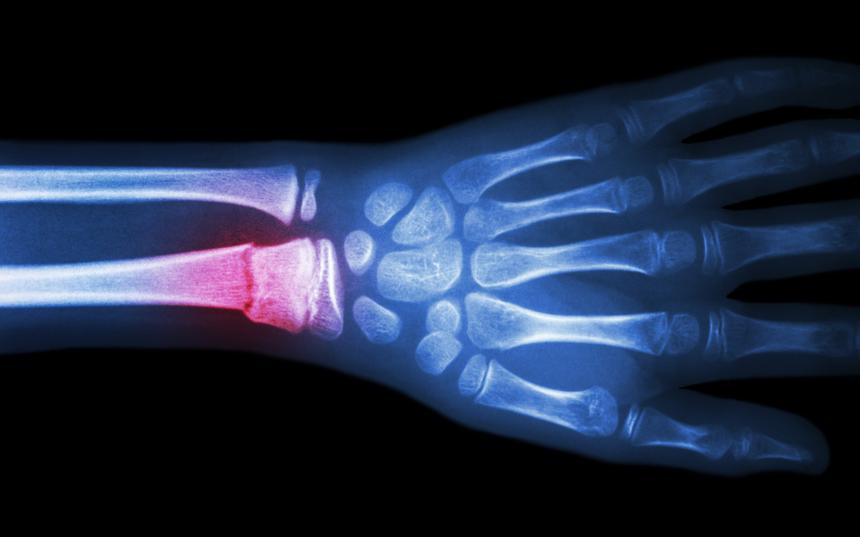

Охлаждение травмированной кости крысы на пять градусов позволило в два раза ускорить ее восстановление, выяснили ученые из России. Такое воздействие увеличивает приток крови и иммунных клеток к месту травмы и препятствует образованию отека.

Сейчас криотерапия — воздействие холодом — широко используется в хирургии (к примеру, при борьбе с раком), физиотерапии и консервации. Охлаждение препятствует формированию отека и уменьшает боль, так как изменение температуры влияет на нервные клетки, уменьшает воспаление и увеличивает потенциал местного иммунитета. Однако практичных способов лечить подобным методом кости пока нет.

Исследователи из МГТУ им Н.Э. Баумана, НМИЦ травматологии и ортопедии имени Н.Н. Приорова и Сеченовского университета просверлили в костях задних лап 12 крыс отверстия диаметром в два миллиметра. Затем модельных животных начали лечили при помощи криотерапии — охлаждая кожу в месте травмы прибором «Холод-01», применяемым в физиотерапии и косметологии. Одну группу крыс лечили два раза в неделю, другую — один.

Через шесть недель две группы сравнили. Выяснилось, что быстрее всего заживление происходило у той группы, к которой чаще применялась криотерапия. При этом криотерапия влияла и на конечности, которые не лечили — динамика восстановления кости была значительно лучше, чем в контрольной группе (у таких крыс лапы не охлаждали). По мнению ученых, изложенном в статье в Journal of Thermal Biology, это вызвано тем, что воздействие холодом влияет не только на костные клетки и сосуды в месте дефекта, но и на иммунные клетки в окружающих тканях и в организме в целом.